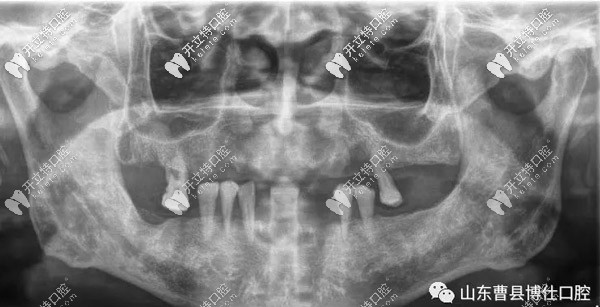

口腔上下只剩7顆牙,對(duì)飲食帶來(lái)了很多不便,經(jīng)檢查發(fā)現(xiàn)徐大爺因患牙周病導(dǎo)致牙齒松動(dòng)、牙齦萎縮、牙槽骨吸收。

經(jīng)過(guò)博仕口腔的于院長(zhǎng)與山東腔醫(yī)院、濟(jì)寧醫(yī)院口腔科和省外醫(yī)生的診斷,采用了7D微創(chuàng)速導(dǎo)種植技術(shù)。